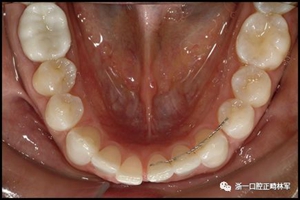

一顆或兩顆尖牙位置的橫向變化可能發(fā)生在與每顆牙齒粘合的小弓絲上,并且在極軟弓絲(圖3)和柔性螺旋弓絲(圖4)上都可以看到。較大直徑的弓絲會產生不同類型的橫向變化。較硬的弓絲與更小的弓絲相比,在尖牙之間產生更多的相關關系。弓絲的扭曲會導致尖牙的往復運動和弓形的歪斜(圖5)。相對較硬弓絲的向下偏斜可以通過尖牙產生擴張(圖6)。

圖3.極軟弓絲完全完好,在多個空間平面上的拱形歪斜,右側尖牙的面部傾斜以及右側側切牙和中切牙在相反方向上的扭矩:A,頰面視圖; B,咬合面視圖。